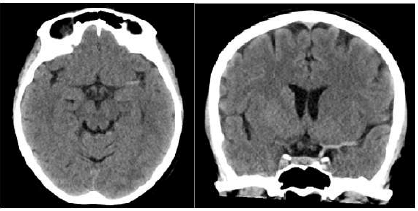

Um homem de 64 anos de idade, sem comorbidades conhecidas, há 3 horas apresenta dificuldade para movimentar o braço direito e para andar, além de relatar sensação de formigamento do lado direito do corpo e apresentar dificuldade para conversar. Familiares negam história de traumatismo craniano. Na admissão do paciente, foram obtidas as seguintes informações: temperatura axilar de 36,5°C, pressão arterial de 130 mmHg x 66 mmHg, frequência cardíaca de 80 bpm, saturação de oxigênio de 96%, glicemia capilar de 88 mg/dL e Glasgow = 15. O paciente estava consciente e orientado em tempo e espaço; pupilas fotorreagentes; movimentos oculares preservados; força motora grau III em dimídio direito e discreta redução da sensibilidade tátil ipsilateral; apagamento do sulco nasolabial à direita; ptose da pálpebra direita; diadococinesia preservada; afasia grave. Foi feita uma tomografia, a qual é exibida a seguir.

Nesse caso clínico, assinale a alternativa que apresenta, respectivamente, o achado exibido na tomografia, o escore do NIHSS e o melhor tratamento para esse paciente.